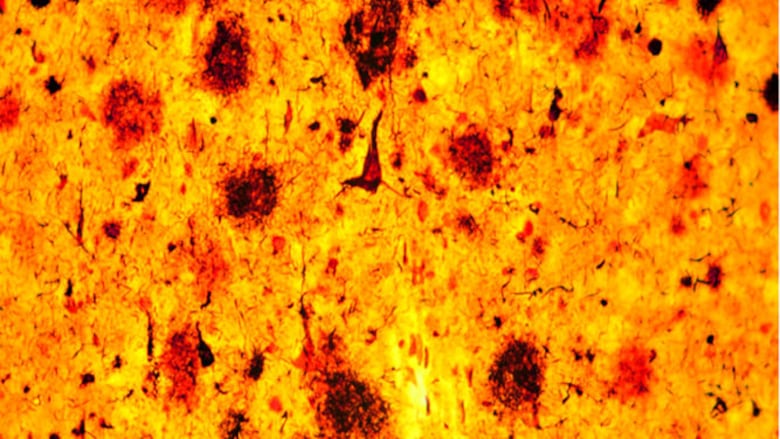

A nivel molecular, se han asociado algunas proteínas con el desarrollo de la enfermedad, como la beta amiloide, que se acumula afuera de las neuronas y hace que se dé una disrupción en la comunicación y la muerte neuronal. Y dentro de las células, está la proteína tau, que estabiliza la estructura de las neuronas.

“Ha habido mucha investigación para ver si se puede detener que se acumule la proteína beta amiloide fuera de las neuronas, o prevenir que la tau dentro de las neuronas se desestabilice”.